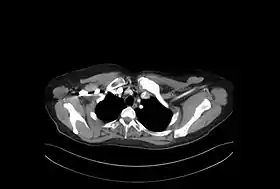

En las radiografías y otras técnicas de imagen (TAC o RMN) puede observarse crecimiento –hiperostosis- y esclerosis de los extremos mediales de las clavículas. Igualmente, pueden observarse áreas osteolíticas y áreas esclerosas. Similar afectación se puede observar en el esternón, en especial en el manubrio y en los segmentos anteriores de las costillas. Fuera de la pared torácica se han descrito hallazgos similares en los cuerpos vertebrales –con imágenes de espondilodiscitis, osteoesclerosis y osificaciones paravertebrales-, en la mandíbula, en huesos largos –sobre todo metáfisis de fémur distal y tibia proximal- y afectación de sacroilíacas. En los huesos largos la imagen es semejante a la osteomielitis crónica, pero sin abscesos, ni secuestros óseos.[11]

Aporta gran información la gammagrafía ósea, siendo es muy típico el patrón de hipercaptación esternoclavicular simétrica en "cabeza de toro", donde el manubrio esternal representa el cráneo y las articulaciones esternoclaviculares y las clavículas corresponden a los cuernos.[15]